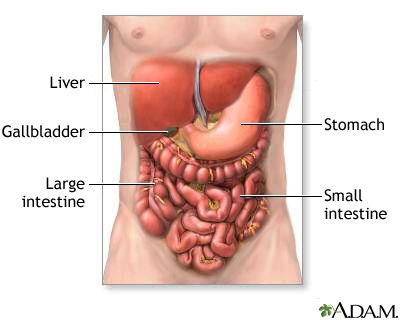

Ascites is the build-up of fluid in the space between the lining of the abdomen and abdominal organs.

Ascites often results from high pressure in certain veins of the liver (portal hypertension) and low blood levels of a protein called albumin.

People with certain cancers in the abdomen may develop ascites. These include cancer of the appendix, colon, ovaries, uterus, pancreas, bile ducts, and liver.